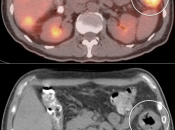

Metastases:

The most common sites of metastatic disease include the lymph nodes (regional & distant), liver, lung, peritoneal cavity, bones, brain and adrenal glands.